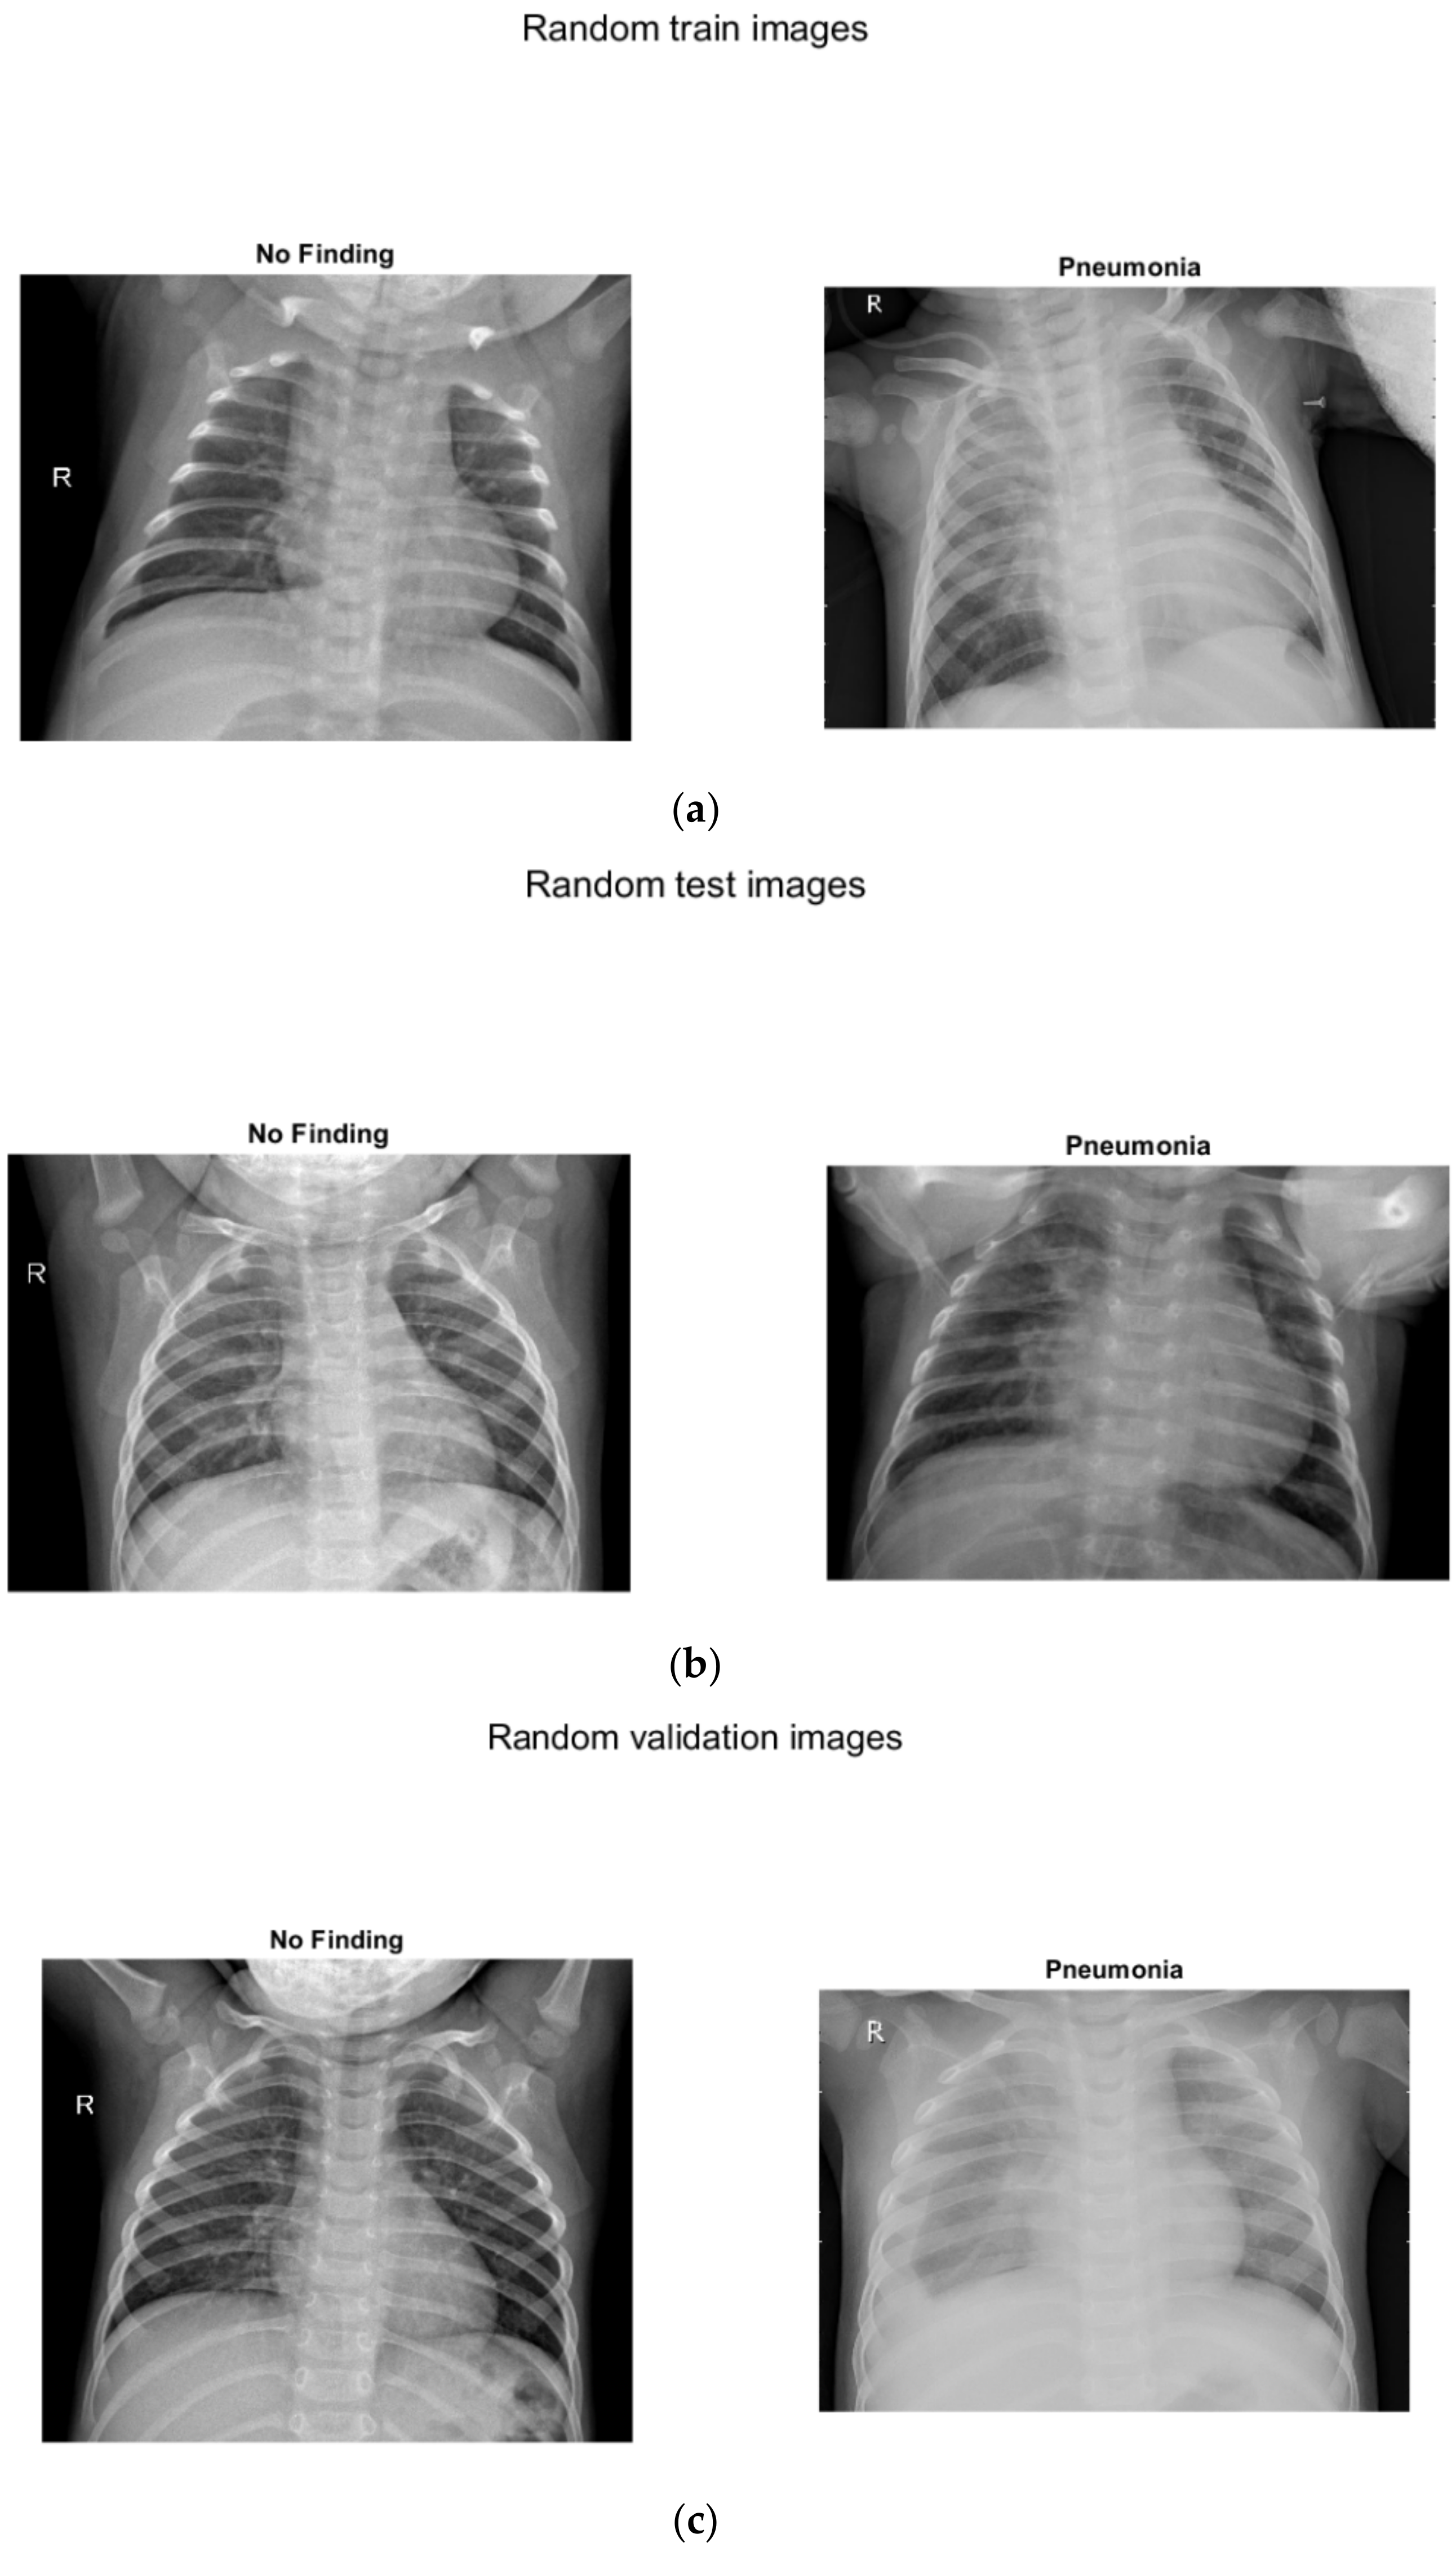

Three separate images show sample images with and without pneumonia of children up to 5 years old (Figure 4): (a) for training, (b) for testing, (c) for verification.

Figure 4.

X-ray images with and without pneumonia of children up to 5 years old: (a) for training, (b) for testing, (c) for verification.